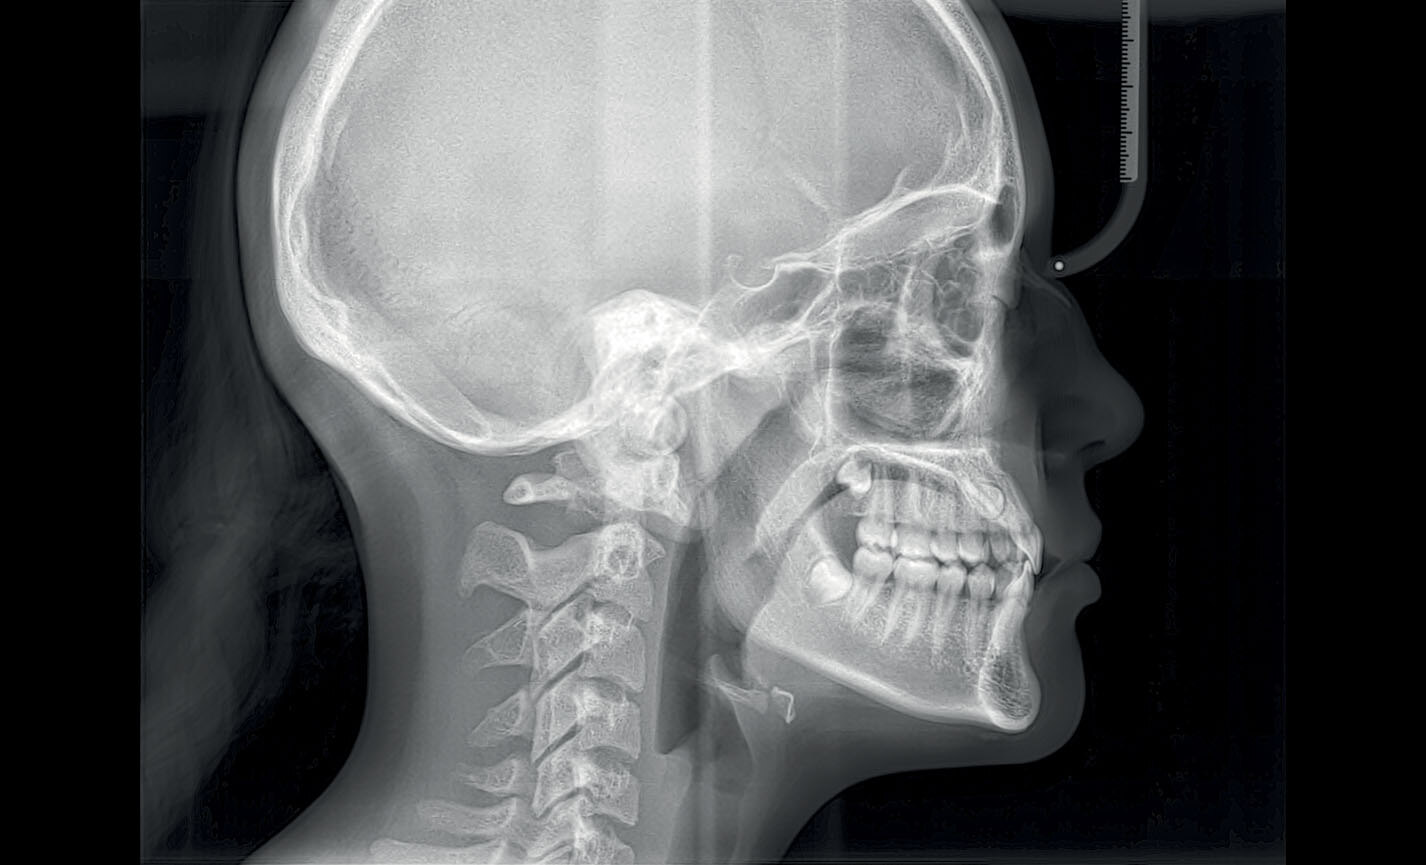

Téléradiographie

Latéro-latérale : avec détails des os et des tissus mous en évidence, fondamental pour les études céphalométriques.

Téléradiographie

Antéro-postérieure : pour investiguer les asymétries et les malocclusions en vue d’un traitement correct.